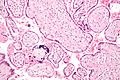

Mikrograf posteljične infekcije (CMV-placentitis).